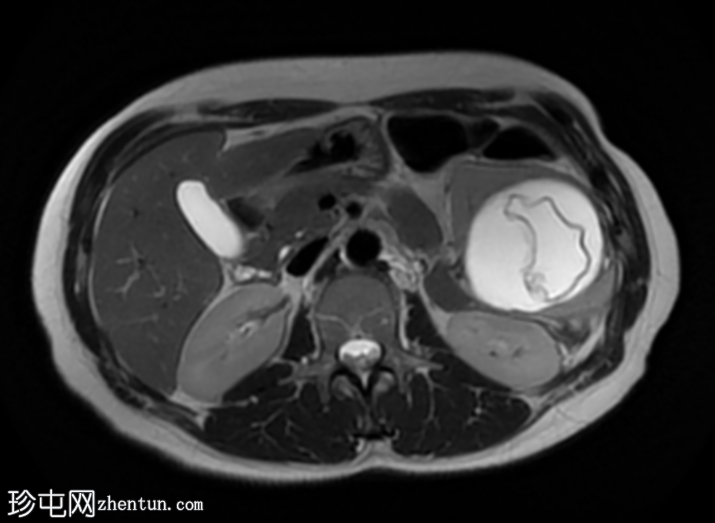

轴位

ADC序列

肝脏肿大,可见多发性双叶肝囊肿。

脾脏肿大,可见多发性大囊肿,内层脱离。

肝脾包虫囊肿的典型

影像

学表现。